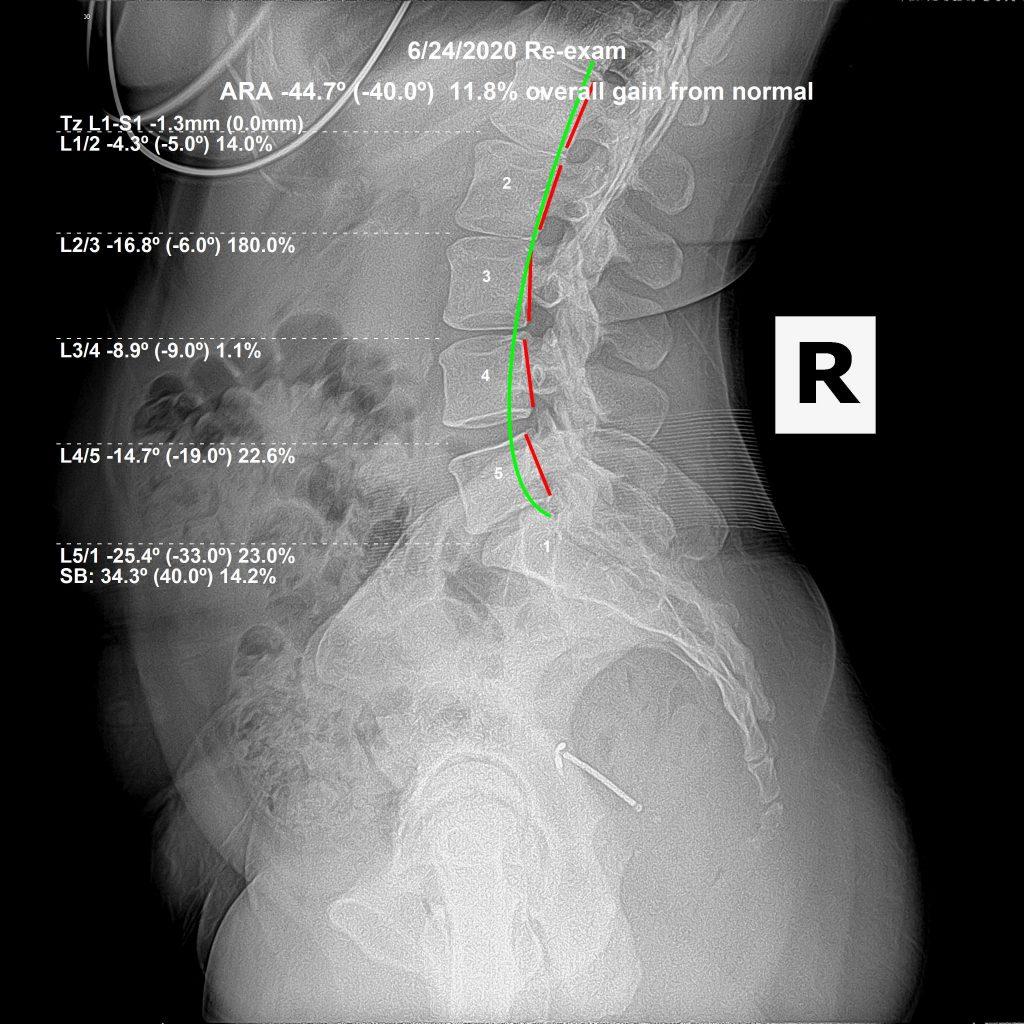

This case was an amazing restoration and I was so happy to see both the changes on x-ray, but also the changes in her overall health and function. The patient is a 43 year old female, who works in the service industry. Service industry jobs require long hours on your feet, and carrying heavy loads in awkward positions. When you combine those work related stresses with a subluxated, misaligned spine, you have the recipe for failure.

The top x-ray shows a severe loss of lumbar curvature (lordosis), as well as a significant degeneration of her L5 disc. The worse the lordosis, the more stress on the disc, the faster the disc is going to wear away.

We started her on an initial 6 month corrective care plan, with spinal adjustments 2x/week. Initially, we had to perform McKenzie Disc Therapies to move the disc material away from the sensitive nerve tissue. After she became functional again, we no longer performed the McKenzie maneuvers and stuck to the spinal structural correction.

Principle 6 – There is no process that does not require time

Principle 6 of Stevenson’s 33 Chiropractic Principles states that there is no process in the body that does not require time. Breakdown takes time to occur. Health and healing equally take time to happen as well. Luckily restoration happens faster than breakdown. As you can see by the second x-ray, we reversed and restored her curvature to almost normal / ideal. By itself, that is a great outcome. When you combine it with better digestive function (she lost 7 lbs just because her digestive tract started operating properly), better rest, more energy, and clearer thought (her mental fog went away), she regained Quality of Life – she regained function.